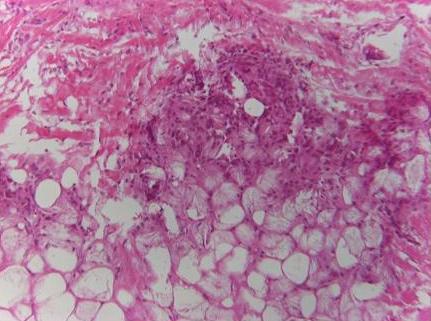

Figura 2. Steatonecrosi del tessuto adiposo sottocutaneo con formazione di cristalli aghiformi (biopsia cutanea) |

Maschio, nato a termine da taglio cesareo per segni di sofferenza fetale dopo gravidanza normodecorsa, peso alla nascita 3100 g, punteggio Apgar 5/6/7 a 1/5/10 min, viene trasferito in Unit� di Terapia Intensiva per distress respiratorio e sottoposto a ventilazione meccanica per 12 giorni. Durante la degenza presenta sepsi, piastrinopenia grave (27.000/mmc), ipertensione polmonare, per cui viene effettuata terapia con antibiotica sistemica e viene somministrato ossido nitrico per via inalatoria. All�et� di 19 giorni viene trasferito presso il nostro Reparto per la prosecuzione delle cure. In sesta giornata di ricovero si evidenziano lesioni eritemato-nodulari di pochi millimetri di diametro, dolenti alla palpazione, in sede ascellare e sottoscapolare destra. Nei giorni successivi le lesioni si estendono al volto, agli arti superiori e al torace e assumono dimensioni maggiori, fino a 3 cm di diametro (Figura 1 a,b). L�ecografia dei tessuti superficiali evidenzia �disomogeneit� ecostrutturale del tessuto adiposo sottocutaneo�. I dati di laboratorio evidenziano VES 63 mm/h e PCR 14 mg/dl (vn: <0,6) quali unici elementi significativi. L�ecografia addominale risulta nella norma. Per una migliore definizione diagnostica si decide di effettuare una biopsia cutanea delle lesioni che mostra �steatonecrosi del tessuto adiposo sottocutaneo con formazione di cristalli aghiformi� (Figura 2).

La diagnosi � essenzialmente clinica. Caratteristicamente, le lesioni tendono a localizzarsi nelle aree in cui c�� una prominenza ossea. Nei casi dubbi, a supporto della diagnosi pu� essere di ausilio la biopsia cutanea. L�esame istologico rivela aree di necrosi grassa, infiltrato infiammatorio cronico linfo-istiocitario con cellule giganti multinucleate e formazione di granuloma, adipociti con strutture eosinofile intracitoplasmatiche disposte radialmente riferibili a cristalli lipidici9. L�agoaspirato delle lesioni sottocutanee pu� essere considerato un metodo diagnostico alternativo alla biopsia10. All�esame ecografico le lesioni si presentano come aree di aumentata ecogenicit�. Lo studio con risonanza magnetica si caratterizza per la presenza di zone a segnale ridotto-intermedio in T1 e aree a segnale intermedio-aumentato in T211.